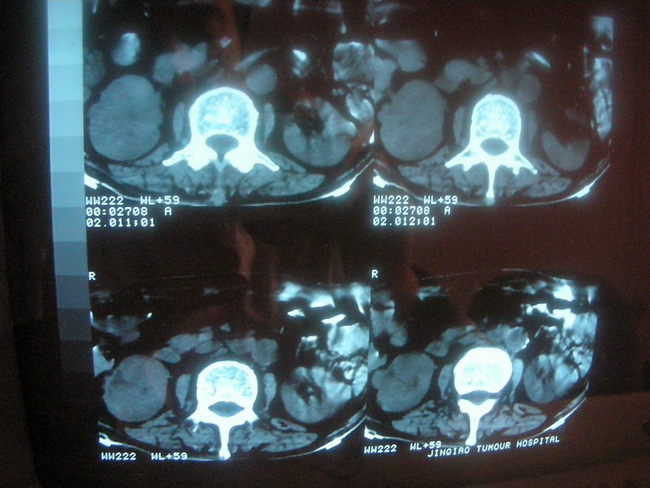

以下是引用卜一在2008-2-16 6:10:00的发言:[br]右肾增大,实质内明显见占位性病灶,并突出体外,密度不均匀。另双肺上叶见散在的斑片 索条及点状结节样致密影,右下肺门区不规则团块,右侧胸腔积液并形成局限性气胸。考虑:1 右肾癌。2 右肺门淋巴结转移及肺内 胸膜转移。3 右上肺陈旧结核。

以下是引用zjzjr在2008-2-16 14:15:00的发言:[br]1 右肾癌伴 右肺门淋巴结转移及肺内 胸膜转移。2右侧胸腔积液引流后改变(可见引流管影)3 双上肺继发型结核。